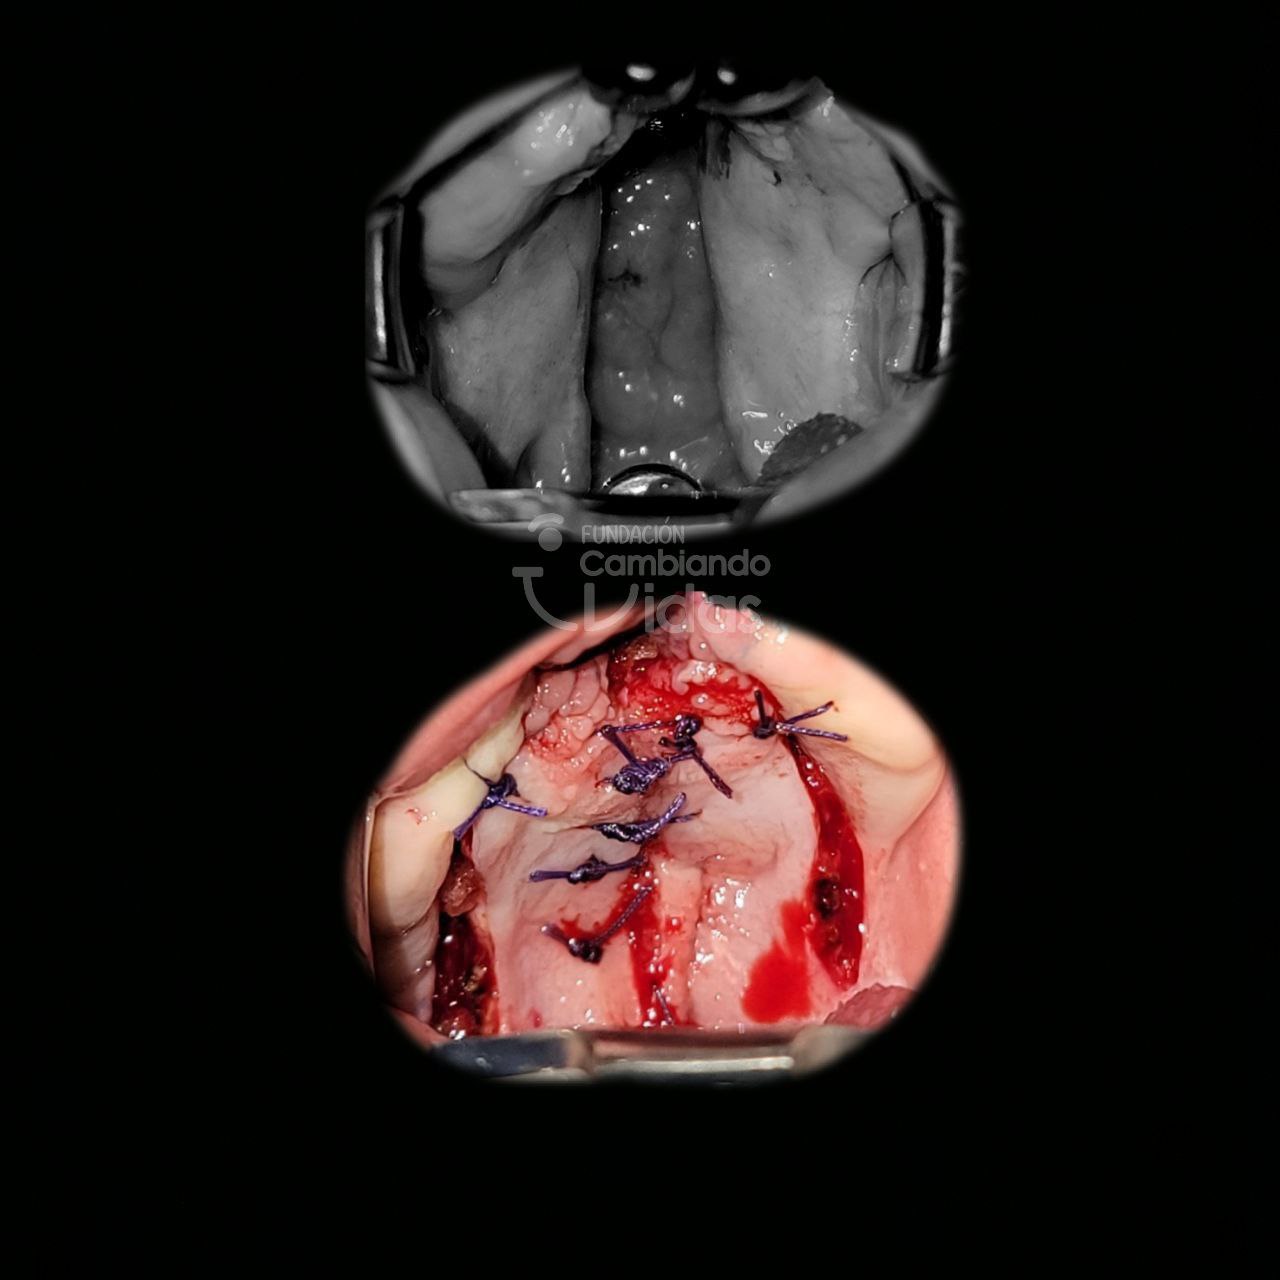

Mia Arias

Intervención Quirurgica: Rinoqueiloplastia Secundaria y Palatoplastia Primaria